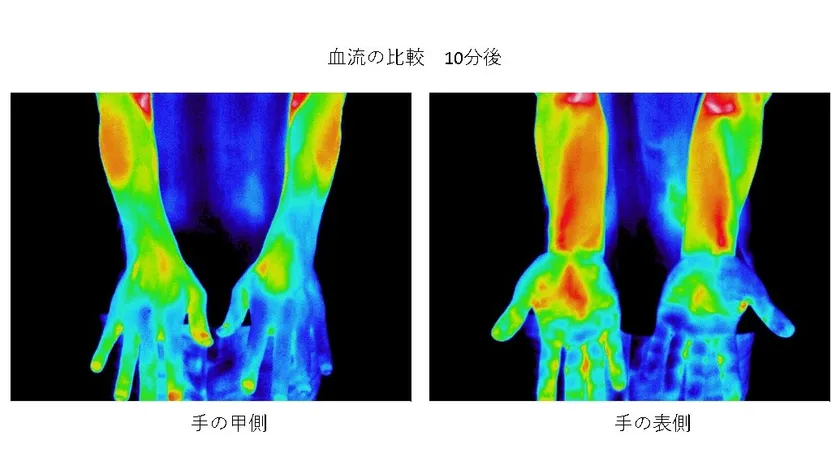

■血流促進・温暖効果

「コロバニィ」に使用している素材はラジウムなどの鉱石類とオーガニック炭が含まれています。

これらの原料は微量ながらも非常に高い遠赤外線輻射熱をもち、シリカ含有率の高いオーガニック炭がもたらす輻射熱とラジウムなどの温泉鉱石により、広範囲の血流を促進します。実験を重ねた結果この効果を認められ、この素材を使用した製品が一般医療機器として登録されており、コロバニィも登録準備を進めています。

図2 温度の変化

図2は両手の“甲”に数センチ角の加工済布片を貼って10分後の様子。左手はただの布ですが、右手は加工した布を貼っています。明らかに右手の血流が促進されているのがわかります。